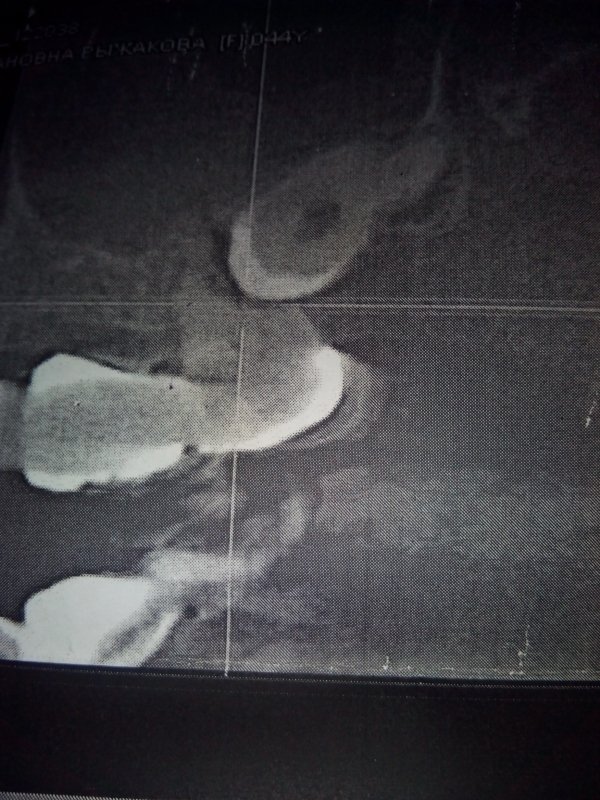

Обращалась к врачам по поводу боли при надкусывании на семерку сверху. Ответ у всех разный. Одни причину ставят - зуб мудрости под десной, который давит на семерку и его надо удалять, другие - больная семерка, а один врач сказал, что никакой восьмерки сверху у меня нет. Я в растерянности.

Я вам уже ответил, боль в седьмом зубе связана с хроническим воспалением на верхушках данного зуба. Обратитесь на очный прием в стоматологическую клинику. Мост необходимо снимать и перелечивать опорные зубы.